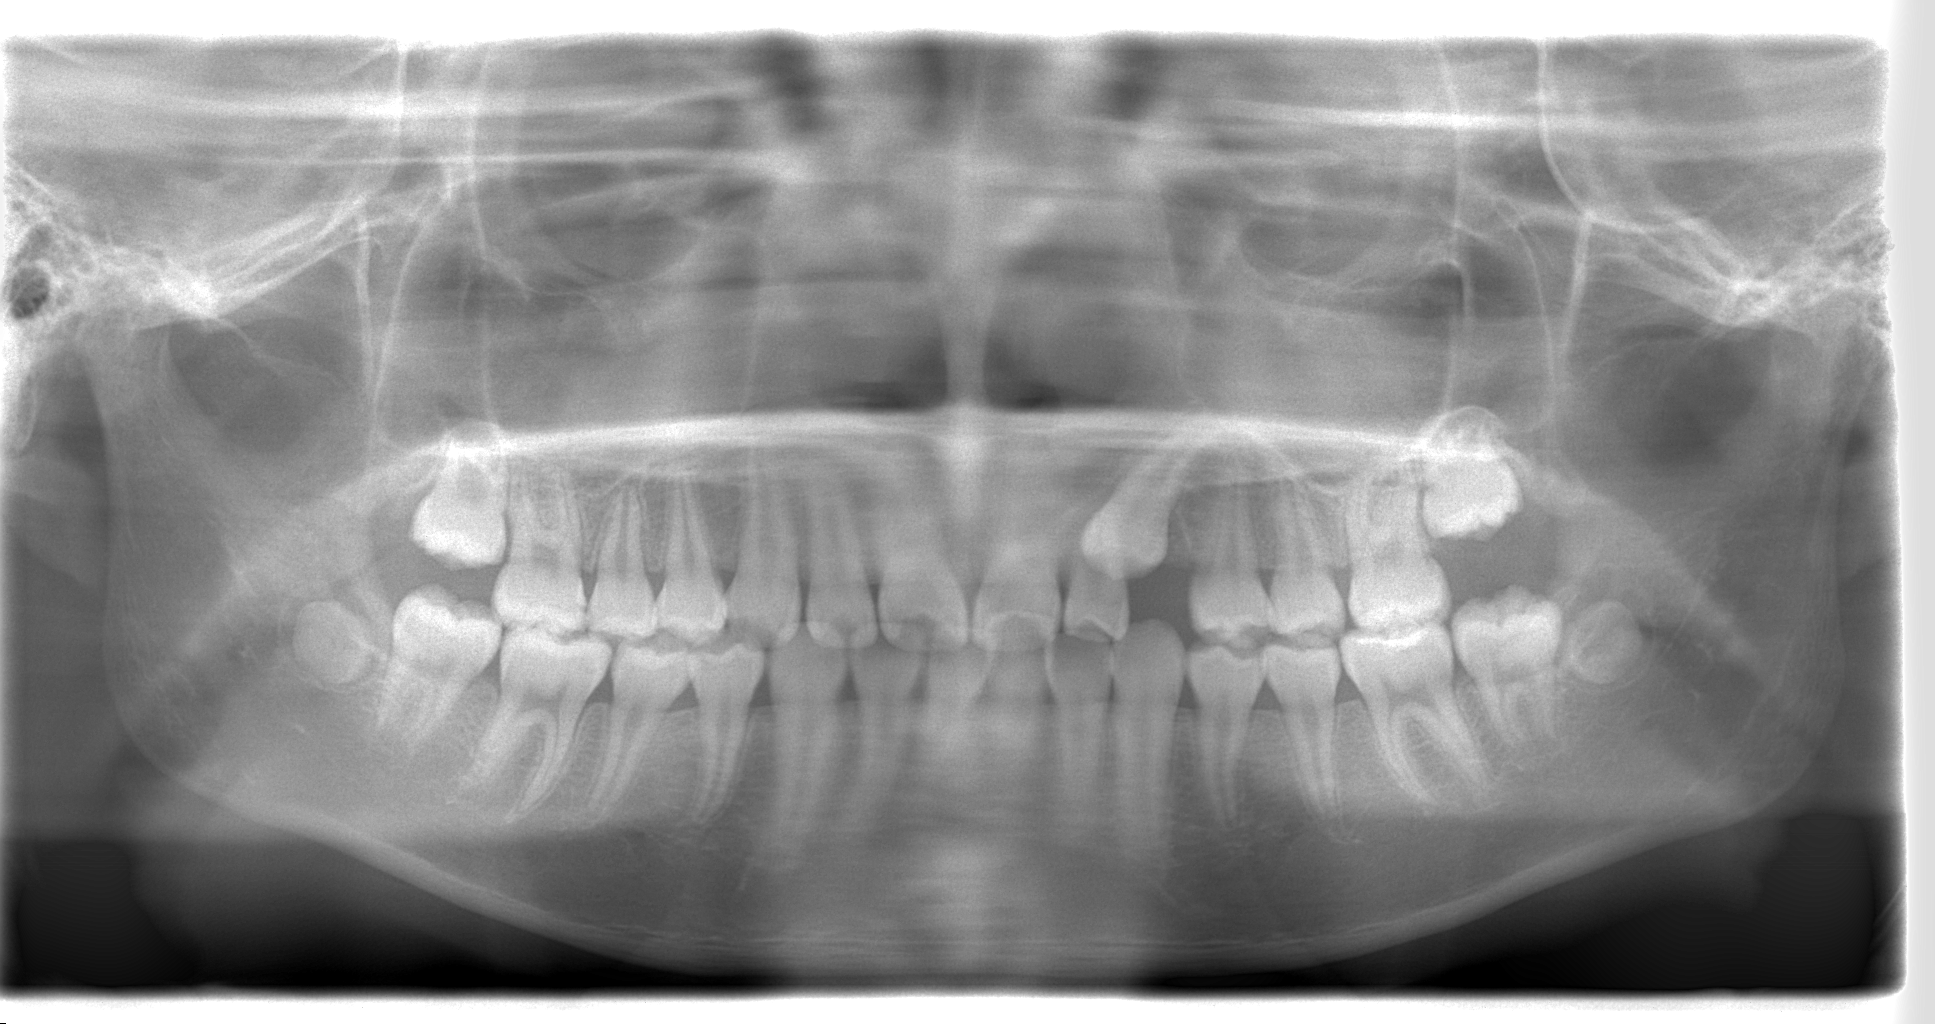

✨犬歯の埋伏歯を正常な位置に誘導しました✨

10歳の女の子、前歯が出ている・少しガタガタが気になるとのことで来院。

犬歯が埋伏していたため、

🦷 外科処置で開窓を行い

🦷 ブラケット装置で牽引

を行いました。

・10歳 女児

・主訴:前歯が出ている、ガタガタ

・治療内容:ブラケット装置+MFT

・治療期間:13か月

埋伏歯とは、歯が生えてくるべき時期になっても歯茎の中に埋まったまま出てこない歯のことを指します。特に犬歯は、永久歯の中でも埋伏しやすい歯の一つです。埋伏犬歯は、レントゲンで確認されることが多く、外からは見えないため気づかれにくいこともあります。

埋伏犬歯が歯茎や骨の中にある場合、外科処置で歯を露出(開窓)させ、その後ブラケット矯正などの装置を使って正常な位置に牽引します。